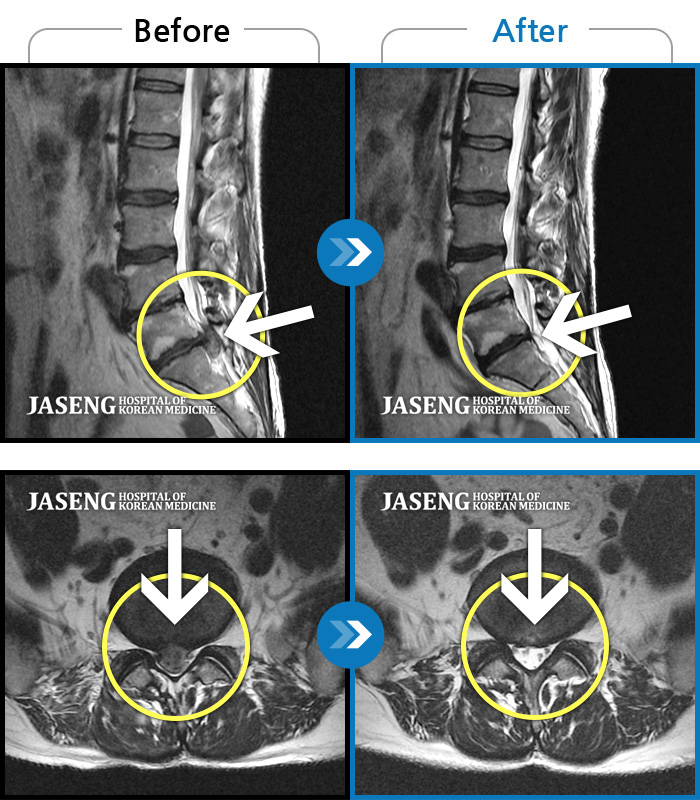

MRI 치료사례

다리가 아프고 힘이 빠져서 지팡이를 짚고 걸어야 했고, 밤에 잠을 못잤어요